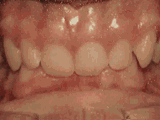

深覆合,咬牙时,上牙盖住下牙的部位过多,影响美观,经过矫正的牙齿是这样的~